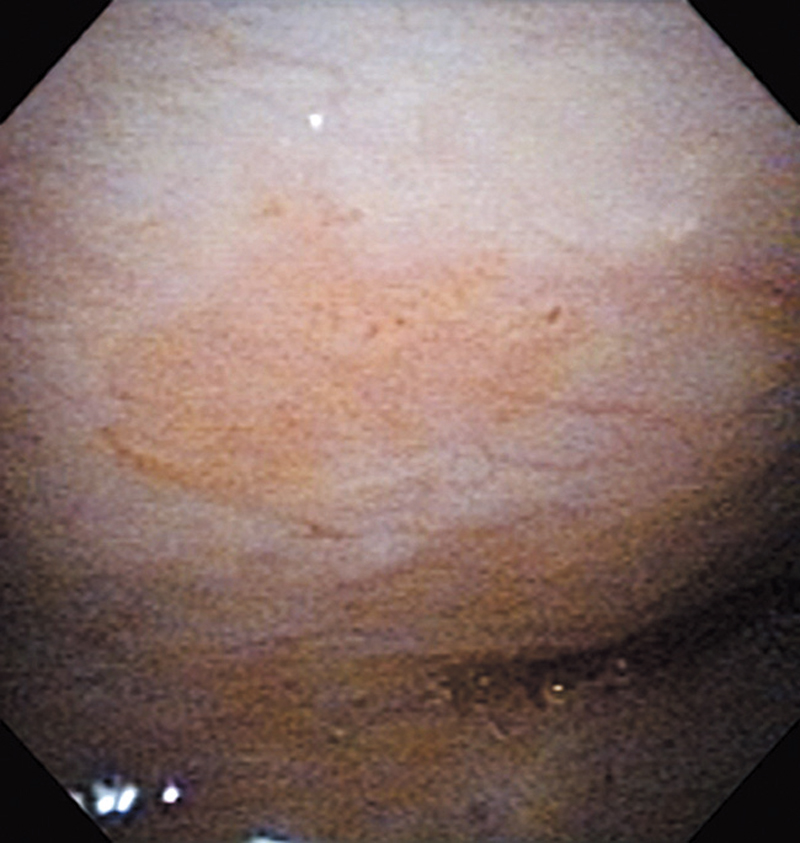

The lesion was detected on the oropharyngeal posterior wall in a periodic laryngopharyngoscopic NBI examination after an esophageal carcinoma surgery.

The NBI image showed a brownish, slightly-elevated lesion. In the conventional white light image, the same area was recognized as a slightly-whitish elevated lesion.

The lesion was treated with endoscopic mucosal resection and diagnosed as a squamous cell carcinoma in situ.